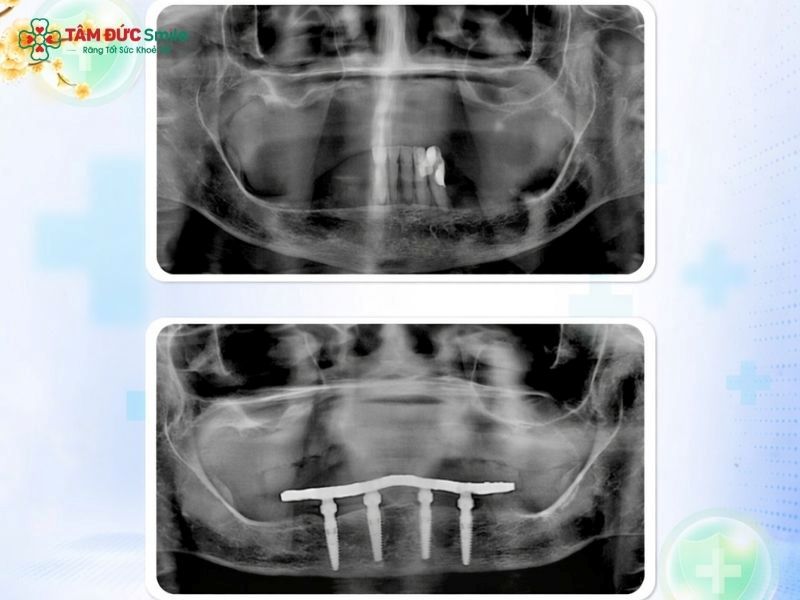

The All-on-4 procedure begins with detailed diagnostics. Advanced imaging technology, such as 3D CT scan for planning, allows clinicians to assess bone volume, nerve positions, and anatomical structures with precision.

This digital workflow supports accurate implant placement technique, minimizes surgical risks, and improves overall treatment predictability. The prosthetic design is also planned in advance to ensure proper occlusion and aesthetics.

During surgery, four implants are placed into the jawbone. The two anterior implants are positioned vertically, while the posterior implants are tilted at an angle. This approach improves stability and avoids critical anatomical areas such as the maxillary sinus or inferior alveolar nerve.